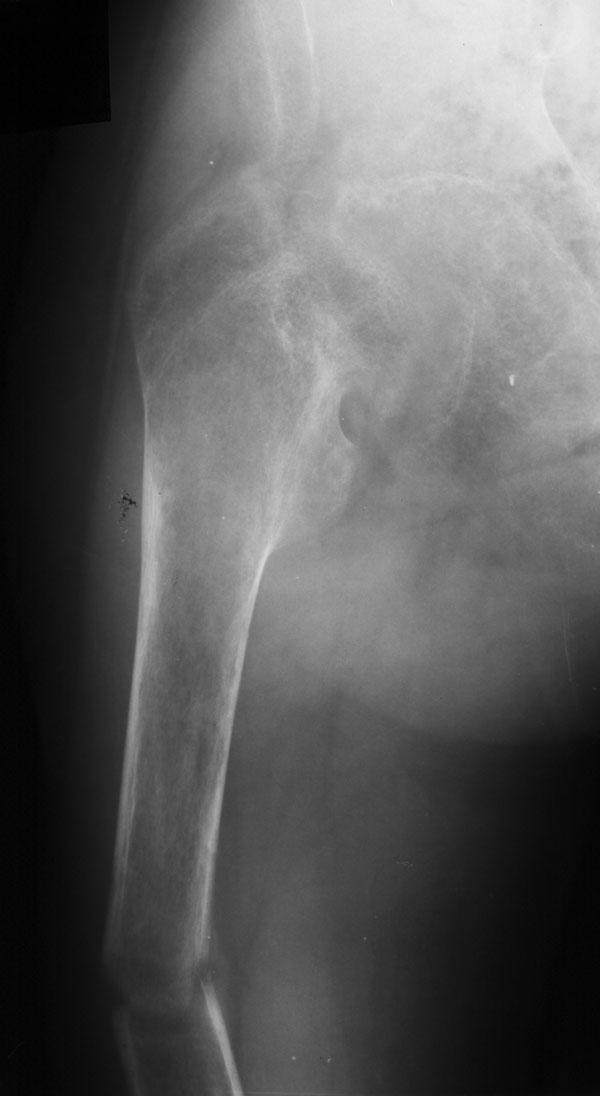

Выписка из амбулаторной карты пациента, 1980 г.р. Находится под наблюдением в поликлинике КНЦ РАН. Состоит на "Д" учёте по заболеваниям: Ювенильный идиопатический генерализованный остеопороз. Деформация грудной клетки за счёт множественных переломов грудины, рёбер. S-образный кифосколиоз грудного отдела позвоночника. Синдром гипофосфатемии неясного генеза. ВСД по кардиальному типу. Инвалид 1-й группы с детства. Последние 4 года не может передвигаться, возникают патологические переломы. Живёт в семье, материально-бытовые условия удовлетворительные. За последние 2 года состояние значительно ухудшилось - усилилась общая слабость, участились патологические переломы, которые не срастаются. Постоянно лежит в постели. Постоянный приём препаратов кальция и диеты с повышенным содержанием кальция, фосфора и белка эффекта не дают. С 11.07.2002 по 30.07.2002 г. лечился в травматологическом отделении АЦГБ с переломом костей правого предплечья со смещением. С 24.08.2002 по 08.09.2002 г. лечился в терапевтическом отделении по поводу острого бронхита с бронхоспастическим компонентом. На сегодняшний день статус. Состояние относительно удовлетворительное. В сознании. Положение вынужденное: сидя в инвалидном кресле, сам встать на ноги и передвигаться не может, туалет только с помощью родственников. Бледный, астеничный. Выраженная деформация грудной клетки, выраженный кифоз и сколиоз грудного отдела позвоночника. Экскурсия грудной клетки ограничена. Участие в акте дыхания вспомогательных межрёберных мышц. Пальпация грудной клетки безболезненна. Деформация всех крупных и мелких суставов за счёт увеличенных эпифизов. Деформация длинных трубчатых костей, мышцы рук и ног атрофичны. Температура - 36,8, ЧД - 29 в минуту. Дыхание жёсткое, проводится во все отделы. Слева от угла лопатки и в аксиллярной области влажные мелкопузырчатые хрипы, в межлопаточной области с обеих сторон свистящие хрипы. Пульс 90 ударов в минуту, ритмичный, симмитричный, слабого наполнения и напряжения. АД 120\80 мм рт. ст. Границы относительной сердечной тупости не расширены. Тоны сердца громкие, ритм правильный. Язык влажный, блестит. Живот при пальпации мягкий, не вздут, симметричный, участвует в акте дыхания, безболезненный. Печень по краю рёберной дуги. Стул регулярный, оформлен, без патологических примесей. Мочеиспускание свободное, безболезненное. Симптом Пастернацкого отрицателен с обеих сторон. Отёков нет. Анализ крови общий 26.08.2002: Hb-146 г\л, Эр.-4,8, ЦП-0,91, Лейк.-6,4, п.-4, с.-45, э.-5, м.-11, СОЭ-4 мм\ч. Анализ мочи общий 26.08.2002: Уд. вес-1025, белок-0,01, сахар-нет, лейк.-0-1 в поле зр., слизь+++, бактерии+. Анализ крови биохимический 26.08.2002: глюкоза-4,9, АЛТ-0,3, АСТ-0,5, биллирубин-11,9, креатинин-44,2, мочевина-3,8, СРБ (+). Анализ крови на микрореакцию - отрицательный. Флюрограмма за 2002: Резко выраженная деформация грудной клетки за счёт множественных переломов рёбер, грудины. Инфильтративных теней в лёгких не определяется. По сравнению с предыдущим исследованием от 01.12.2000 г. - ухудшение: нарастают деформация грудной клетки и позвоночника. ЭКГ за 2002 год: Синусовая тахикардия с ЧСС 88 в минуту. Отклонение ЭОС вправо. Признаки нарушения процессов реполяризации миокарда задней стенки левого желудочка. Повидимому, изменения ЭКГ обусловлены позиционными изменениями, возможно астеничным телосложением. Дополнительные методы исследования. Рентген правого предплечья (17.10.2002): Металлоостеосинтез по поводу перелома обеих костей правого предплечья в н\з: признаки репарации практически не определяются, сохраняется диастаз между отломками. Рентген правого предплечья (24.04.2003): Металлоостеосинтез по поводу перелома обеих костей правого предплечья в н\з: признаки репарации отсутствуют, формируются ложные суставы. Резко выраженный остеопороз. Рентген правого бедра (18.02.2003): Несросшийся перелом правого бедра на границе с\з и н\з со смещением отломков под углом открытым кнутри. Формирующийся ложный сустав. Выраженный остеопороз костей. Рентген правого бедра (24.04.2003): Угловое смещение отломков правого бедра увеличилось. Признаки репарации крайне вялые: по наружному краю отломков формируются замыкательные пластинки - ложный сустав. Выраженный остеопороз.